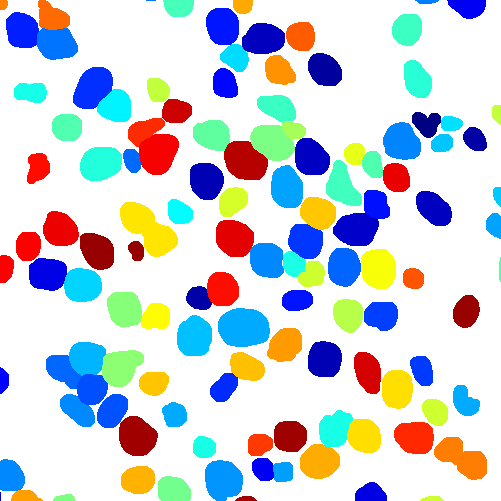

As an essential part of digital pathology, histopathology image analysis is playing increasingly important role in cancer diagnosis, which can provide direct and reliable evidence to diagnose the grade and type of cancer. This paper deals with nuclei segmentation, an important step in histopathological image analysis. The purpose of nuclei semgentation is not only counting the number of nuclei but also obtaining the detailed information of each nucleus. So unlike nuclei detection, here the outputs are the contour of each nucleus instead of only the position of their central points. Hence we can exactly extract each nucleus from the image and make it available for further analysis. For example, the features of the individual nucleus and the distribution of nuclei clusters can be used to grade and classify status of breast cancers [3, 4]. Because of appearance variation such as color, shape, and texture, nuclei segmentation from histopathological images could be very challenging, as illustrated in Fig.1, in which it is very challenging even for human to recognize and segment all nuclei within the images. Fig.1(a) and Fig.1(b) illustrate two histopathological images from different organs. Fig.1(c) and Fig.1(d) are two histopathological images from same organ but have different cancer grade.

Figure 6 shows how our method segments the nuclei step by step. The color variety is well controlled by the color normalization procedure. The prediction result shows clear nuclear areas and nucleus boundaries. In the final segmentation result and ground truth image, each nucleus is represented by a different color.